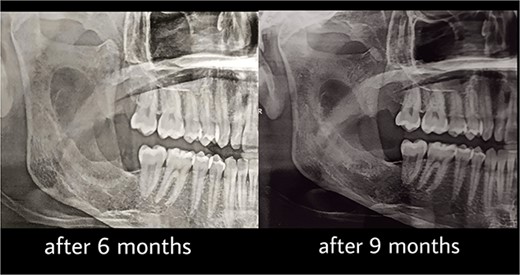

Under general anesthesia, an incision was made around the fistula to remove the overlying mucosa and expose the lesion. A 1 cm size window was made into the cyst cavity (Fig. 3). The cyst lining was sutured to surrounding mucosa. The cavity was kept open using a povidone iodine-saturated gauze, and it was replaced every 2 weeks. Follow-up radiograph (OPG) was recommended after 3, 6, 9 and 12 months (Figs 4 and 5).

Computed tomography after 12 months showed a bone regeneration in the lesion’s area and the cystic lesion has become completely surrounded by thick bony plates.

After 12 months, the second stage was performed to remove the lesion (Fig. 6). Under general anesthesia, enucleation with peripheral ostectomy was performed. A flap was developed to expose the anterior border and most of the lateral surface of ramus. The lining of the lesion was detached from the bony walls. A surgical bur was used to remove bone adjacent to the cystic lining. After enucleation, the cavity was filled with gelfoam and the incisions were closed with 4–0 Prolene suture. The patient returned regularly for follow-up after every 3 months (Fig. 7). The total follow-up period so far was 36 months. Cone beam computed tomography (CBCT) scan after 24 and 36 months showed no evidence of lesion recurrence and great bone formation (Fig. 8).